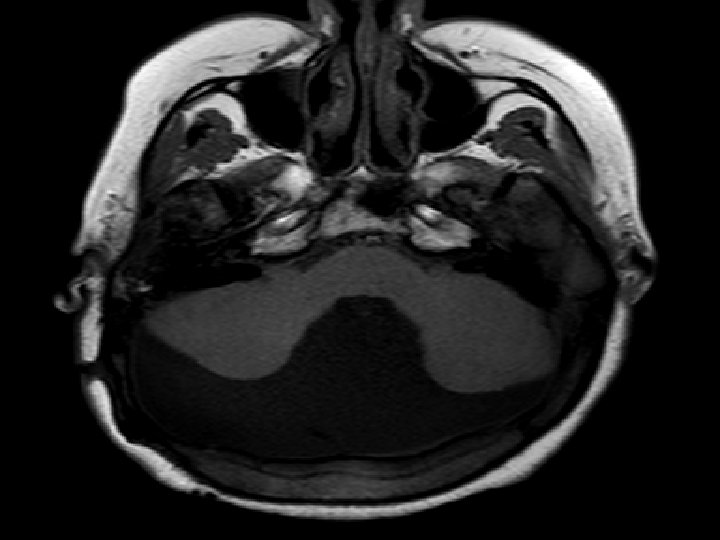

2 - ci xəstə � Qız uşağı � Yaş : 5 � Klinik əlamətlər : Hidrosefaliya, əqli inkişafdan geriqalma, hərəki aktivliyin pozulması � Diaqnoz : klassik DW

T 1 sagital kəsikdə arxa çuxurda böyük ölçülü kista, hipoplastik soxulcan kist üzərində yuxarıya çevrilib. Beyincik yarımkürələri və beyin kötüyü hipoplastikdir, incəlmiş ənsə pulu

T 2 şəkildə hidrosefaliya, arxa çuxurda böyük BOM kistası incəlmiş ənsə sümüyü və hipoplastik beyincik yarımkürələri qanad şəkilli

T 1 aksiyal kəsikdə yan mədəciklərin böyüməsi , arxada kista